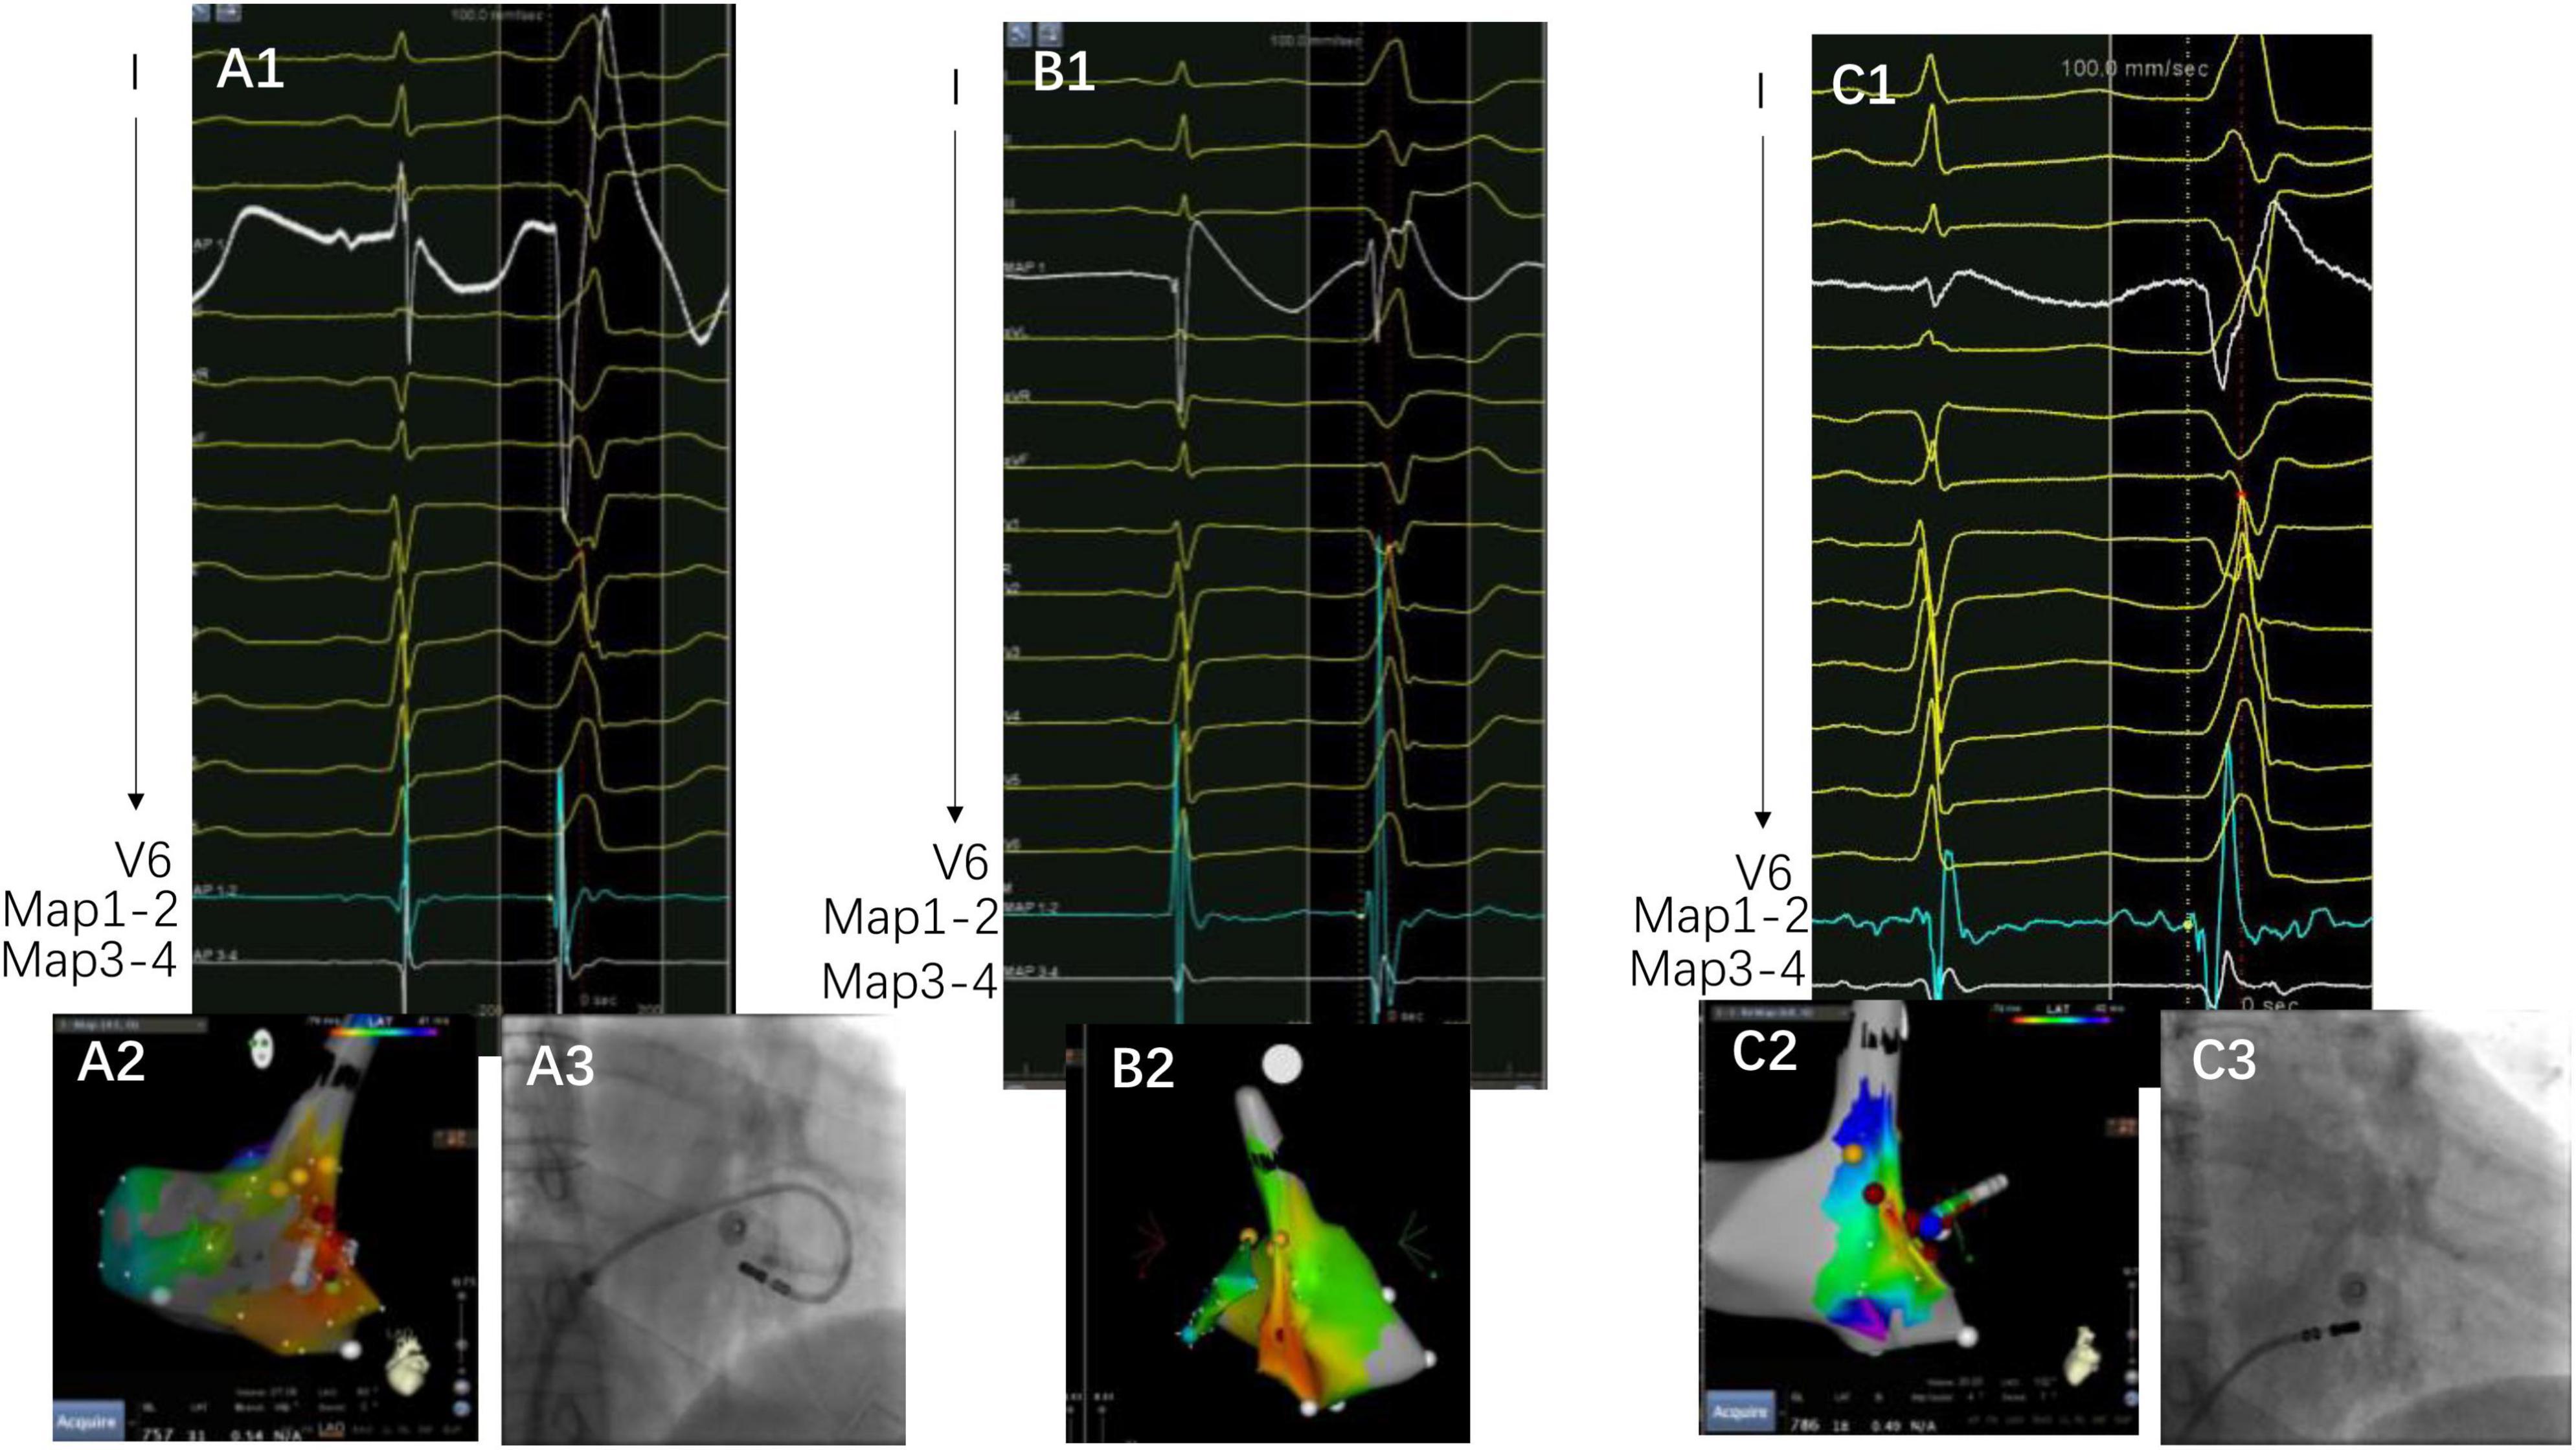

The complex anatomical arrangement has been translated into various VAs delineated by different groups. Hiroshi Tada et al. reported that the septum was the preferential site of origin for tricuspid annulus VAs (3). The latter has also been reported as the basal septum of the right ventricle for a distinct VA-originating structure by another group (10). Meanwhile, several studies have described the endocardial ablation of VAs from the left side, in which the structure was named “the basal infero-septal process of left ventricle” (7, 9), “left ventricular septum” (11), or “left ventricle adjacent to the membranous septum” (12). Additionally, the so-called basal infero-septal process has been successfully ablated from the atrial side (Figure 3) (13, 14).

Figure 3. A case of VAs ablated from the low Koch’s triangle. Panels (A1–A3) are target activation, three-dimensional map, and fluoroscopy image at the under-valve area, respectively. The target electrogram precedes the QRS onset by 14 ms, with a small “a” signal at the target electrogram. Panels (B1,B2) are the earliest activation and three-dimensional map, respectively. Notice that the target electrogram has a 6 ms prematurity compared with QRS onset without the “a” potential. Panel (C1) is the target electrogram at the low Koch’s triangle preceding QRS onset with 28 ms. There is also an “a” potential at the target. The yellow points depict the area recording His in Panel (C2) and the blue point depicts the mapped activation. Notably, QRS demonstrates subtle changes after ablation on the right side of the under-valve area. Panels (A3) and (C3) depict the image contrast of the under-valve area and above valve area (low Koch’s triangle).

It was found that the VAs was eliminated using the under-valve approach in 36 patients (70.6%) after a 12 month follow up. Additionally, most of the patients demonstrated a small “a” potential at the target site, which suggested that these tachycardias could be classified into a septal group of VAs from the annulus (Figure 4). Nevertheless, basal septal area VAs has unique characteristics compared with arrhythmias from other parts of the annulus due to the following facts. First, sequential ablation from both sides of the septum was required in 47% of patients due to the exit shift, which reflects a deep or even intramural location of the VA origin in some cases (Figure 5). When catheter ablation on the tricuspid valve is unsuccessful, a catheter inversion technique of the under-valve approach should be attempted for mapping and adequate contact and stability of the ablation catheter (15). In some situation, an anatomical ablation approach is also a valuable option in basal septum from intramural foci. Meanwhile, the impairment of AV conduction should not be ignored during RFCA delivered to this region. In our study, first-degree atrial ventricular block in the acute period and complete atrial ventricular block 3 months after the procedure were observed in two and one patients, respectively. Second, due to the apical displacement of the septal tricuspid valve relative to Koch’s triangle, some VAs from the septal tricuspid annulus were successfully ablated from the low Koch’s triangle with no complications (14). Third, in those patients that need left-side ablation, a combined strategy employing a retrograde aortic approach and a transseptal approach should be considered. Consequently, based on the unique anatomical and electrophysiological characteristics, a systematic approach for VAs originating from the basal septal area is warranted.